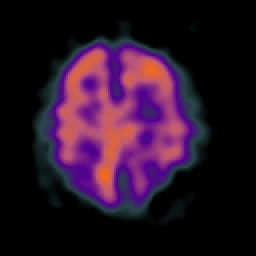

Alzheimer's disease: Perfusion SPECT -- Slice #36

[Home][Help][Clinical][Tour 1][Tour 2] Slice 36